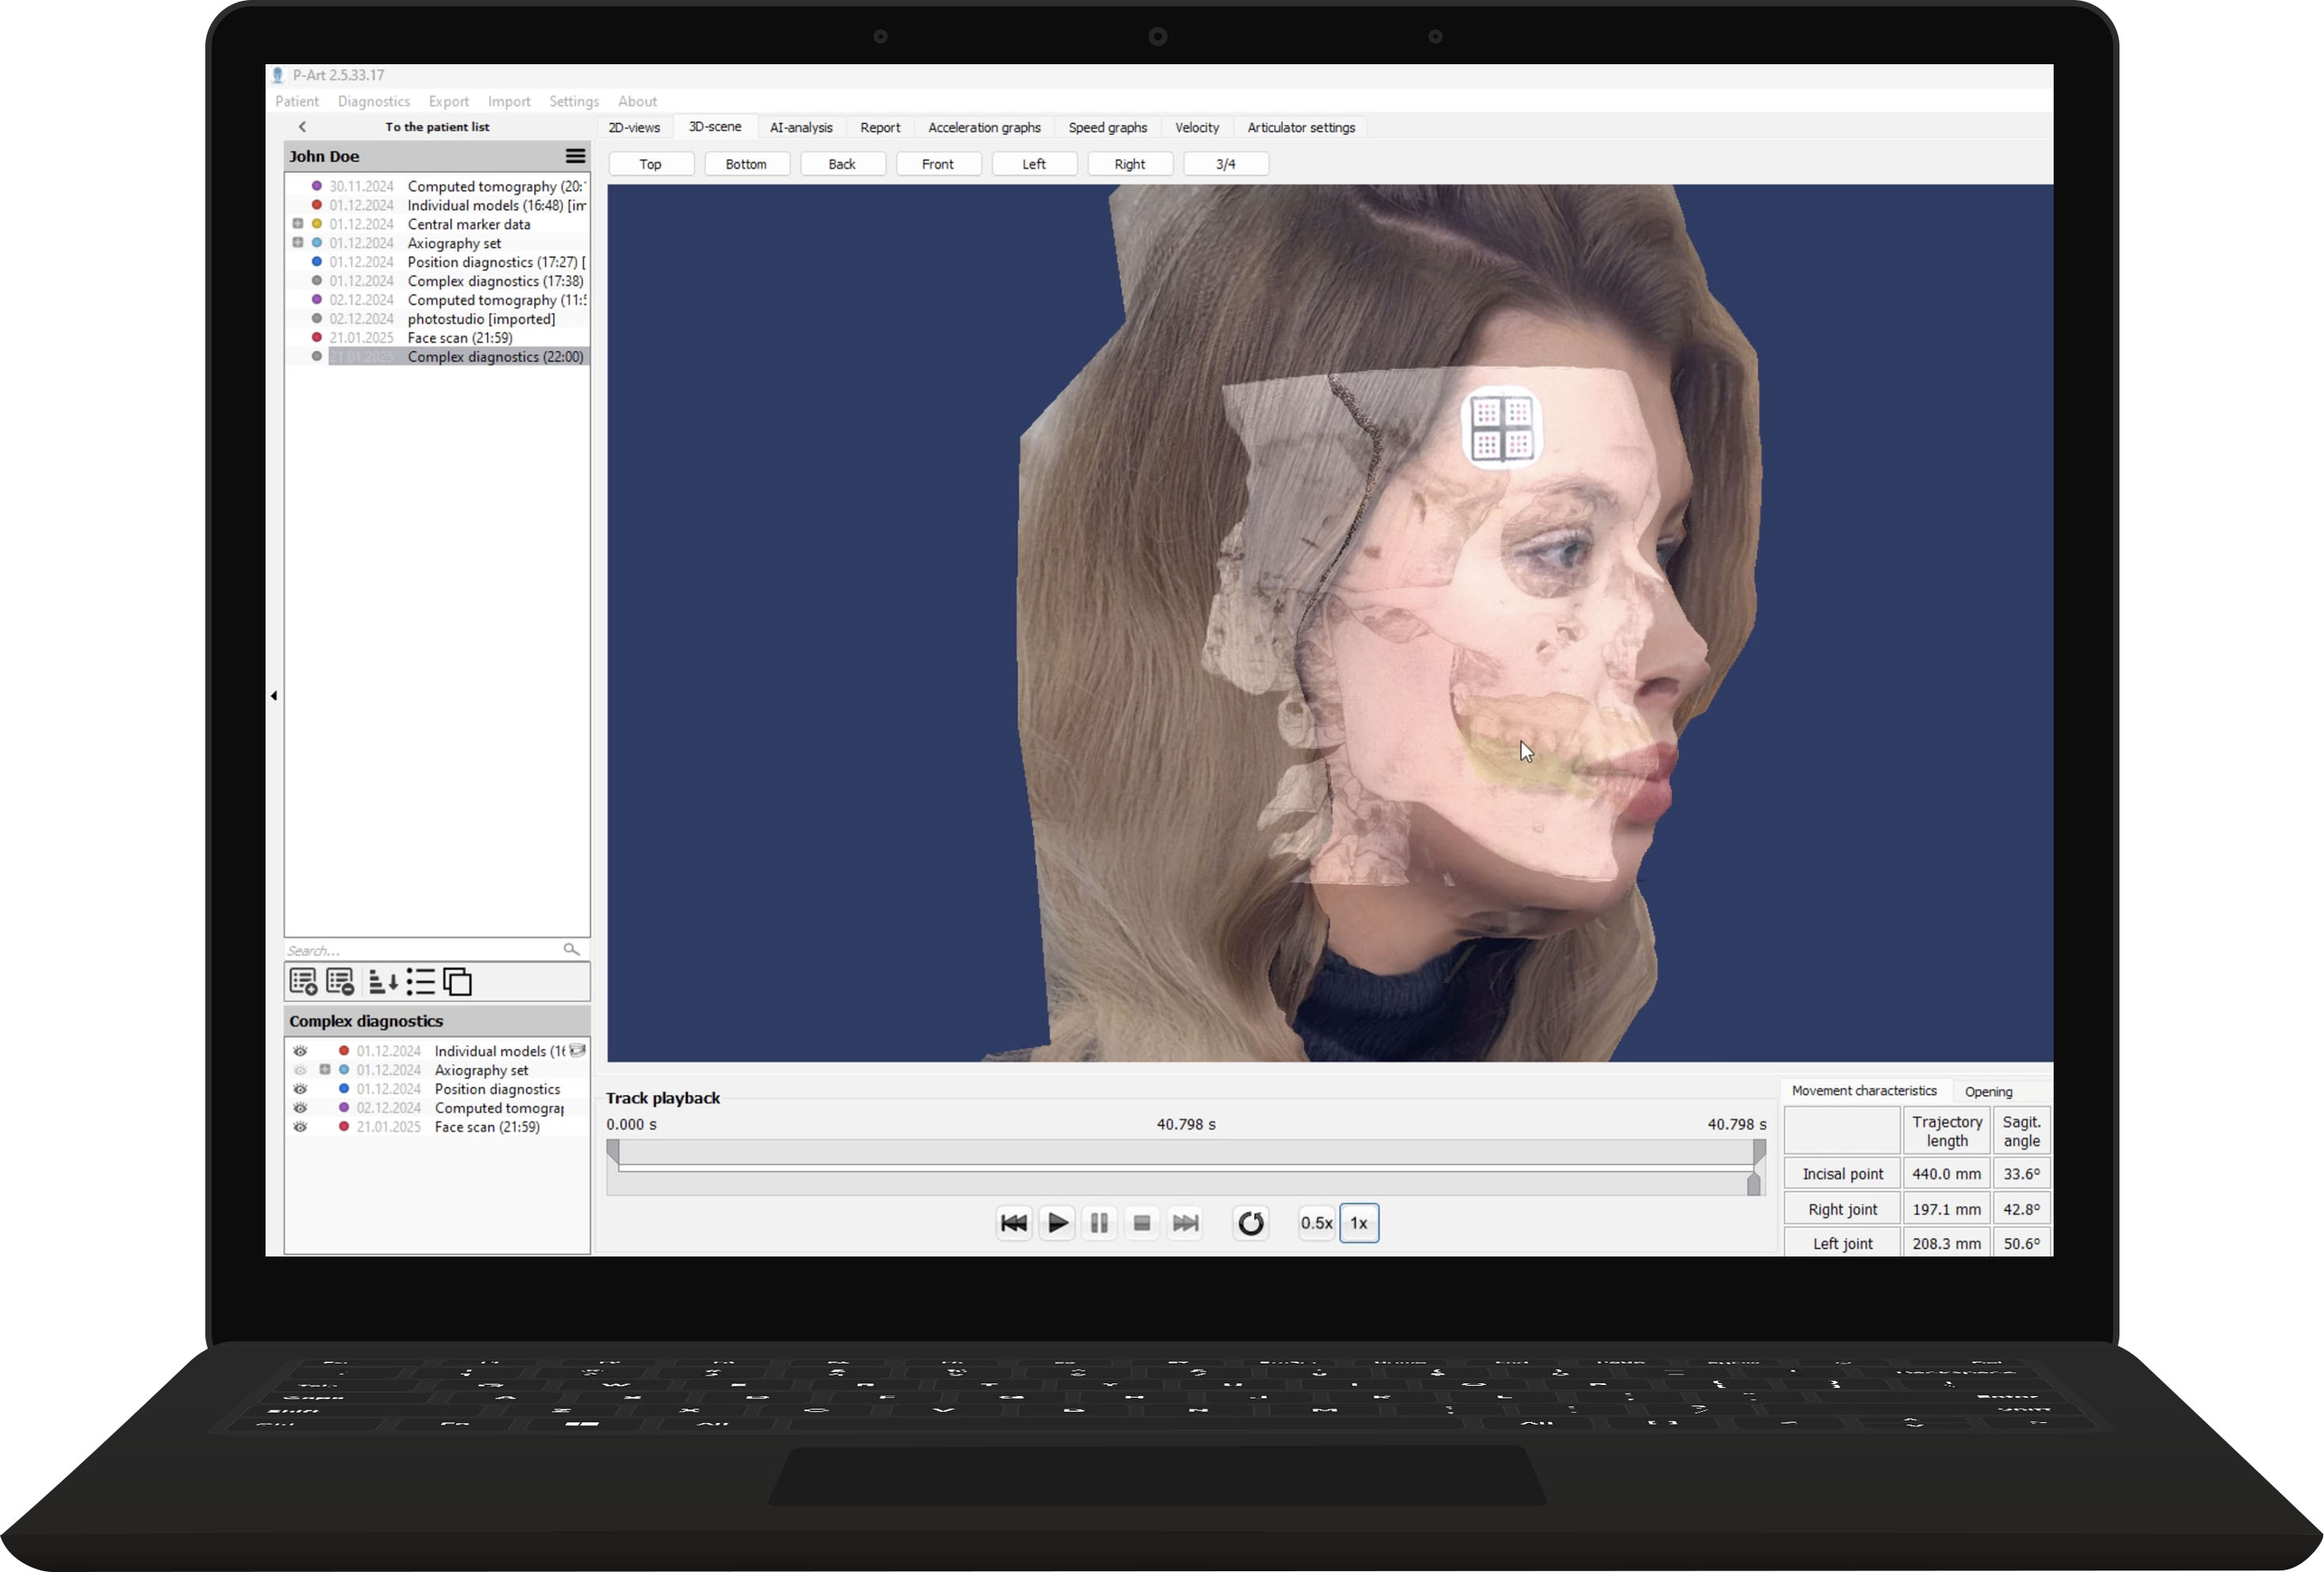

Allows you to work with dynamic data, virtual models, and CBCT data. You can visualize occlusal contacts and all dynamic abnormalities. Using CBCT data, you can determine the bite height and identify joint dysfunctions. You get a virtual patient.

Be sure to try facial scanning

It allows you to analyze aesthetic parameters and align the treatment plan with the patient, considering the new aesthetic guidelines.

Record axiography, make face and tooth scans, import CBCT

Merge all data into one 3D model. See all in real-time animation

Set new jaw place, calculate future position of a jaw. AI will assist you with it

Export whatever you need: CT, tracks, planes with your custom parameters